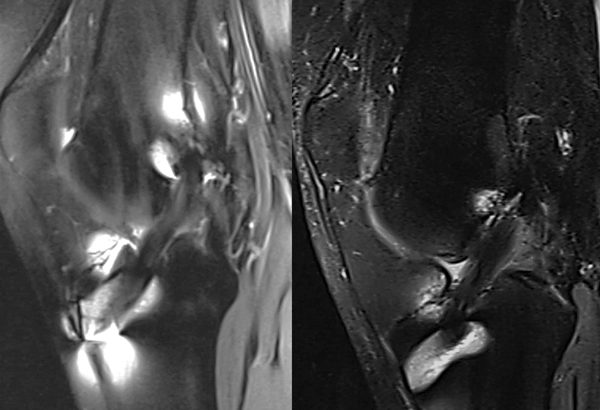

Al sexto mes se realizó RM de la rodilla operada. Se exploraron en una posición extendida relajada con un escáner de RM de 1.5-T (MAGNETOM Esenza A Tim System; Siemens). Las imágenes se obtuvieron con secuencia de densidad protónica con saturación grasa en plano oblicuo y los siguientes parámetros: tiempo de repetición 3000 milisegundos, tiempo de eco 28 milisegundos, ángulo de giro 160, matriz 320 x 272, campo de visión 15 x 15 cm, grosor de corte 3 mm, tiempo de escaneo 2 minutos y 41 segundos. También se obtuvieron cortes sagitales con secuencia de tiempo de recuperación de inversión (IR) con los siguientes parámetros: tiempo de repetición 5730 milisegundos, tiempo de eco 34 milisegundos, ángulo de giro 150, matriz 256 x 230, campo de visión 15 x 15 cm, grosor de corte 3 mm, tiempo de escaneo 2 minutos y 2 segundos. Todas las imágenes fueron importadas a una estación de trabajo con el programa Siemens Software Packages (NUMARIS/4, SyngoMR B17; Siemens), y todos los cálculos se hicieron con este software a partir de los cortes sagitales de cada injerto.

Se midió la intensidad de la señal en el sitio del injerto, así como en otros dos sitios (tendón cuádriceps y aire de fondo a aproximadamente 2 cm anterior al tendón rotuliano). Para cuantificar la intensidad de señal normalizada del injerto del LCA, se calculó el coeficiente de señal de cada sitio de injerto con la siguiente ecuación: CS = (señal de injerto ACL - señal de tendón de cuádriceps) / señal de aire de fondo.10 El mismo investigador efectuó todas las mediciones, ciego en relación a la técnica utilizada para la plástica del LCA (fig. 4).

Figura 4: RM al sexto mes del postoperatorio. Medición del CS en ambos grupos (foto izquierda pertenece al grupo de desinserción tibial, la foto derecha al grupo que mantuvo la inserción tibial).